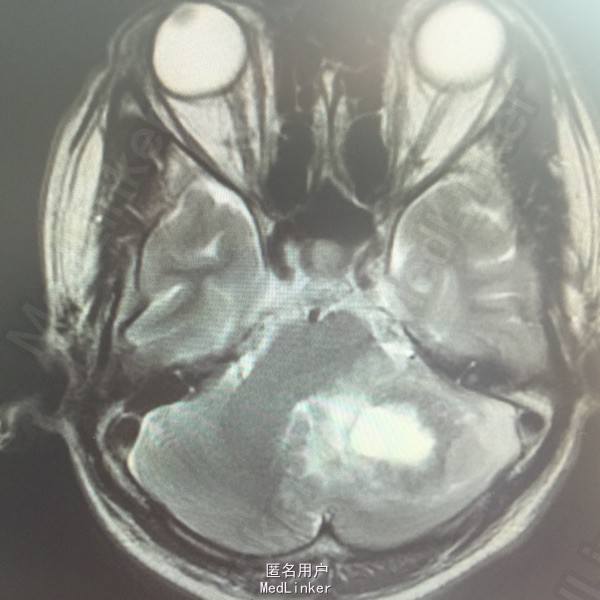

男,54岁,以头痛半个月入院。 现病史:半个月前无诱因头痛,呈胀痛,无呕吐,无意识障碍,病来咳嗽、咳痰,体重减轻约5斤,无发热。 既往史:无特殊。

查体:BP:150/100mmHg,神清语明,两瞳孔等大正圆,直径约3.0mm,光敏,四肢肌力5级,肌张力正常,腱反射艹,左侧共济运动阳性,病理征阳性,脑膜刺激征(-)。 辅查:见下:

肺癌脑转移。 影像解读(影像如何解读是临床工作中非常重要的一环)。 左侧额叶近皮质长Tl长T2信号,局部颅骨缺损,右侧枕叶不规则病灶,TlWl呈中心呈等信号,周围高信号,T2Wl呈高低混杂信号,伴大片水肿,相邻侧脑室后角、胼胝体受压。增强呈不规则环环强化。 已进行局部放疗治疗。